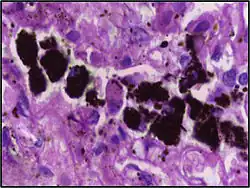

Comparison of pigmented pulmonary macrophages

| Disease | Macrophage name | Macrophage pigment appearance (HE stain) | Usual macrophage location | Associated medical history | Image | Image comment |

|---|---|---|---|---|---|---|

| Respiratory bronchiolitis | "Smoker’s macrophages" | Yellow to light brown and finely granular[4] | Airways (especially respiratory bronchioles) | Tobacco smoking |

|

Smoker's macrophage in center |